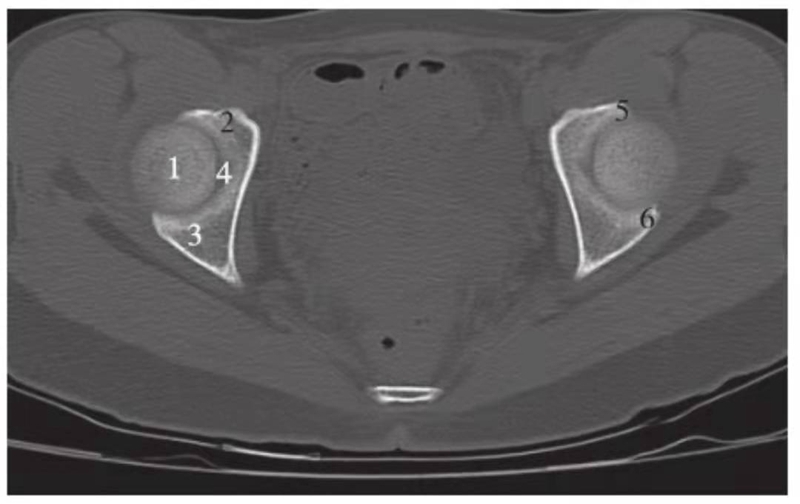

图1 正常股骨头顶部层面(骨窗)

1.股骨头;2.耻骨;3.坐骨;4.髋臼窝;5.髋臼前唇;6.髋臼后唇